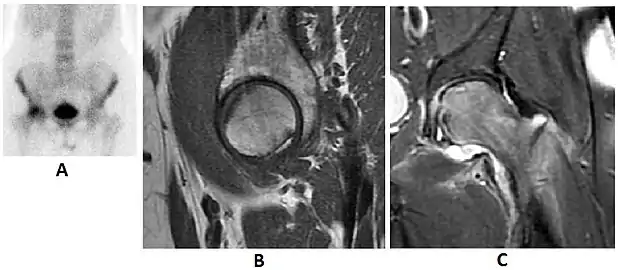

Nuclear Medicine

Bone scanning in people with hip pain can be complementary to other imaging studies, mainly in indeterminate bone lesions to clarify whether it is an active lesion with abnormal radiotracer accumulation. Nevertheless, MRI has replaced scintigraphy in the diagnosis of most of these conditions. An example is stress or insufficiency fractures: increased uptake is usually present in around 80% of fractures within 24 h, and 95% of fractures reveal activity by 72 h following trauma, showing an overall sensitivity of 93% and specificity of 95%. MRI is superior to bone scans in terms of sensitivity (99%-100%) and specificity (100%). Moreover, a bone scan does not provide detailed anatomical location of the fracture, and further imaging is usually required.[1]